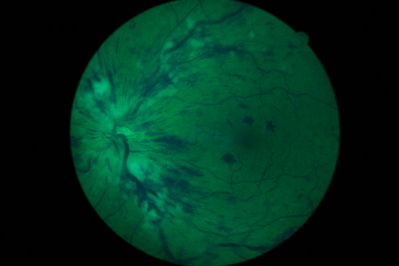

CRVO LE - non-ischaemic - on Presentation

CRVO_red_free.jpg